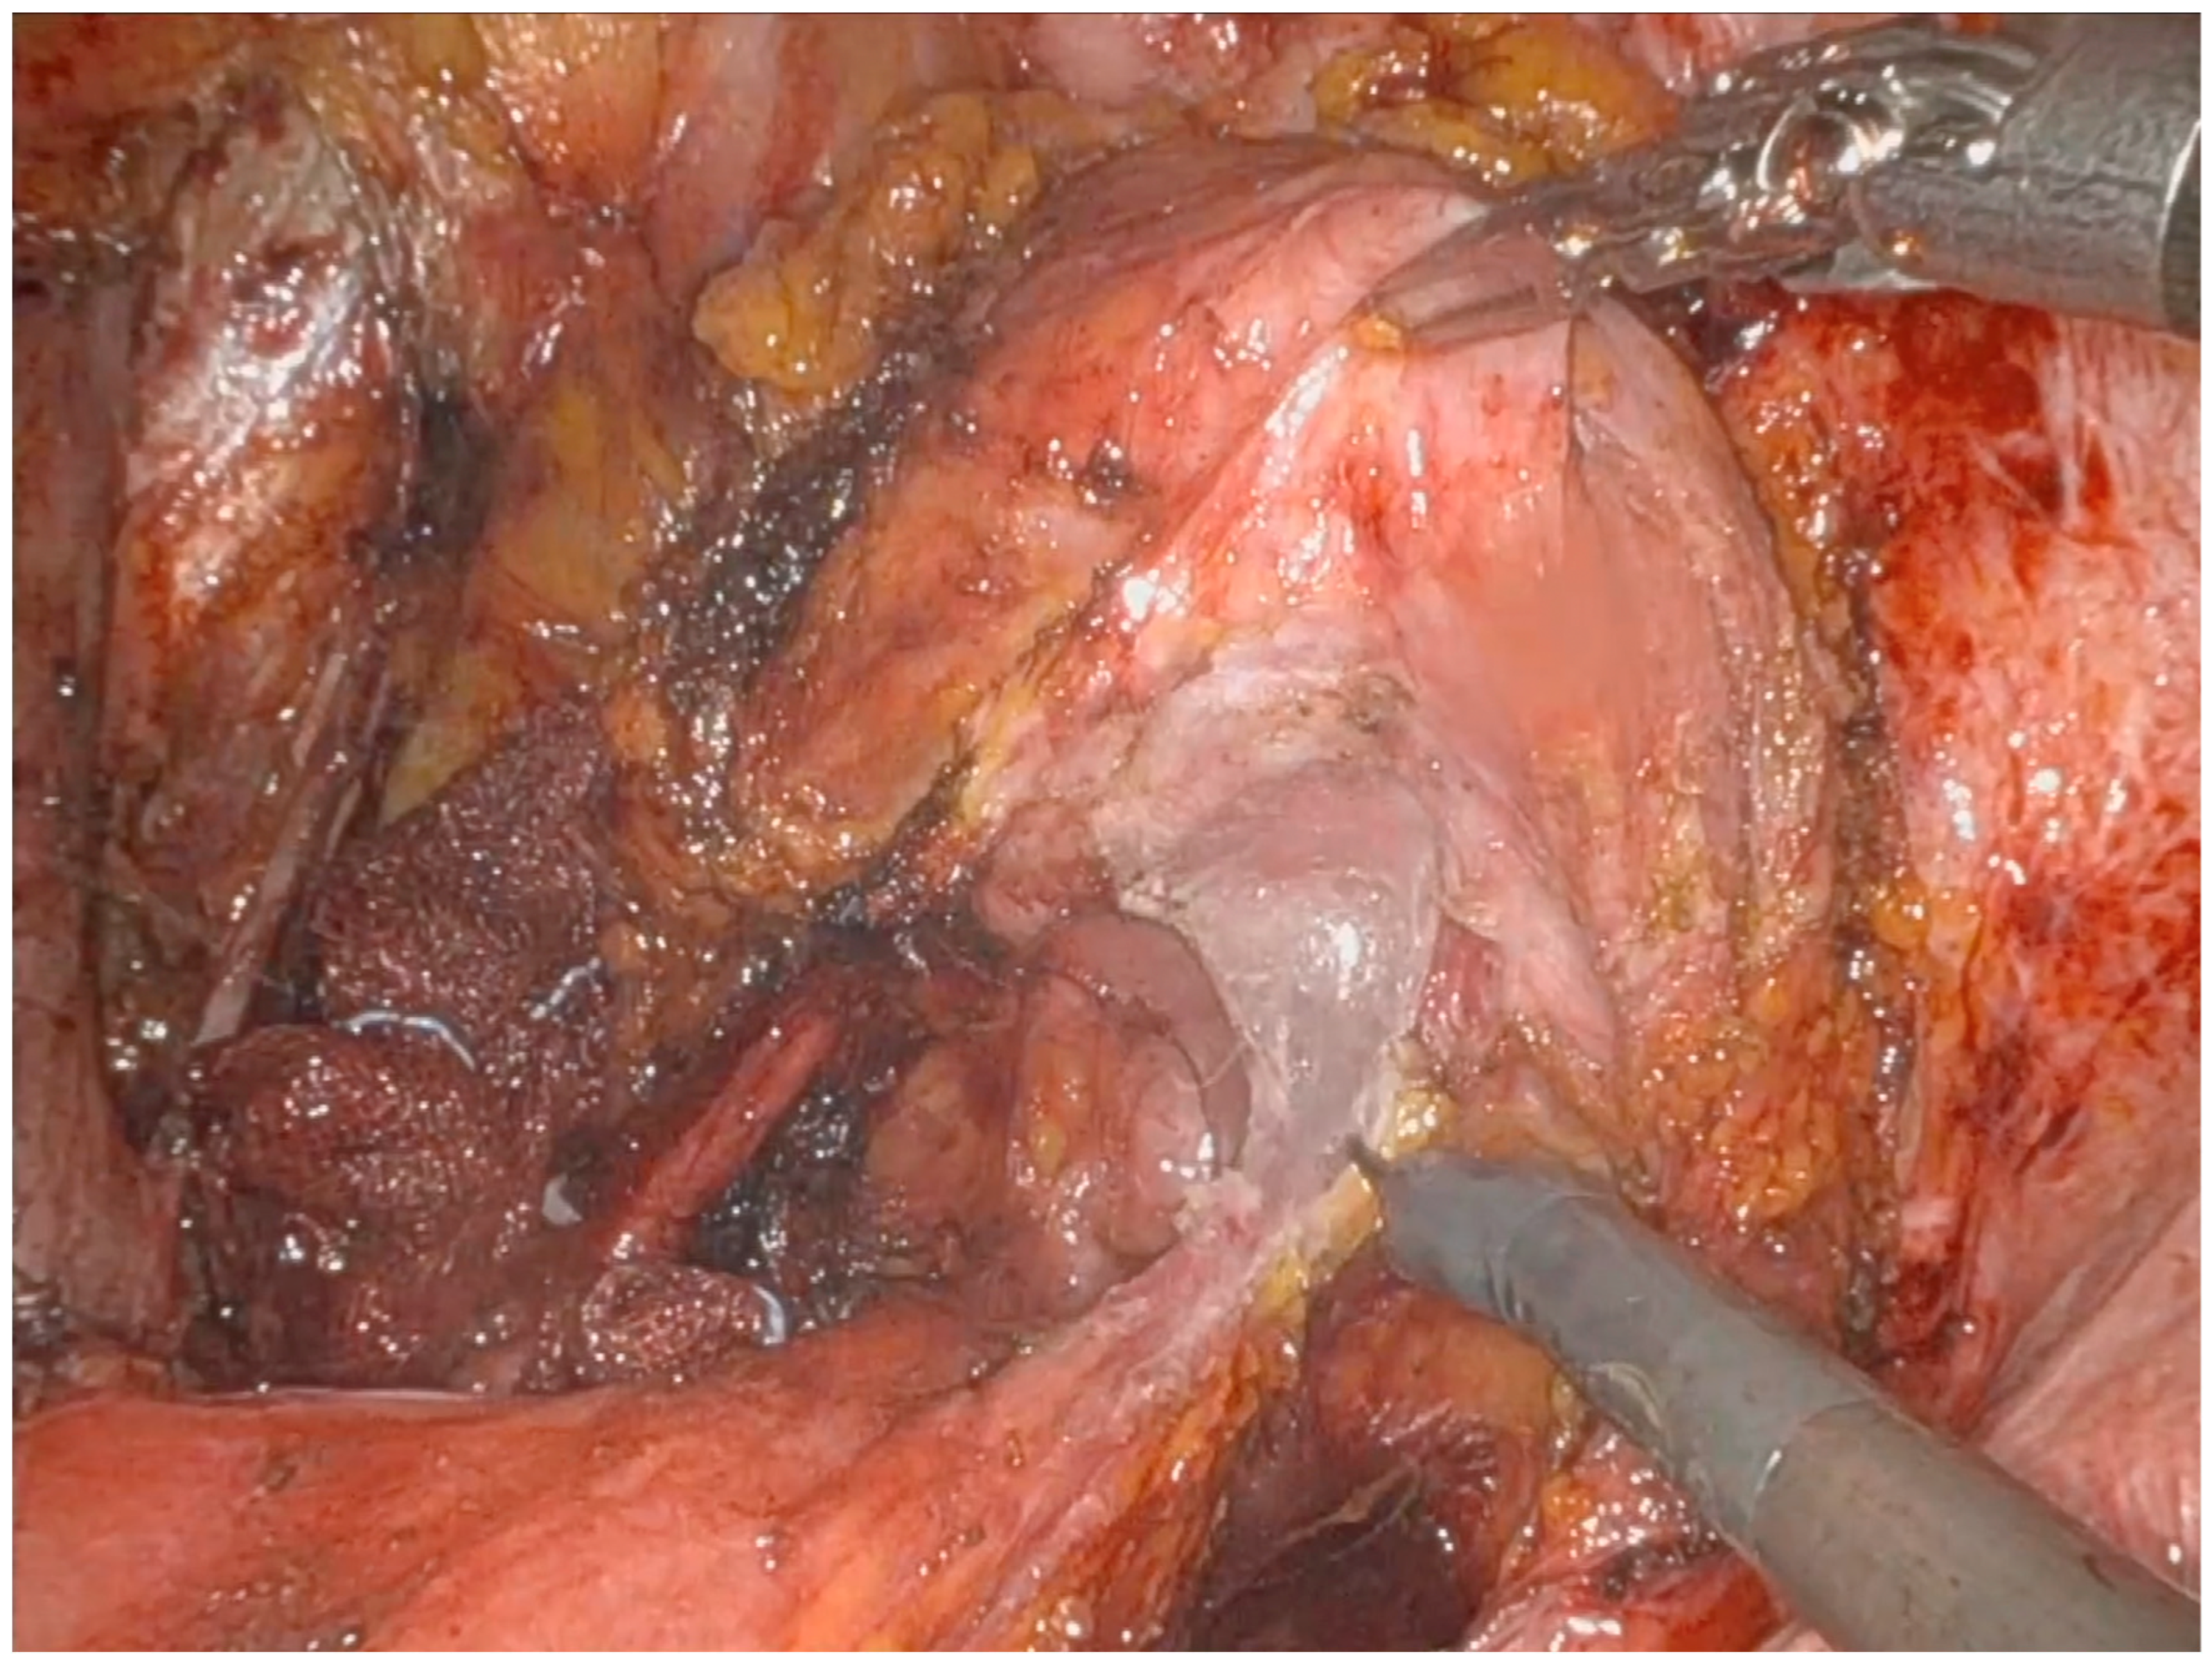

Operative Technique